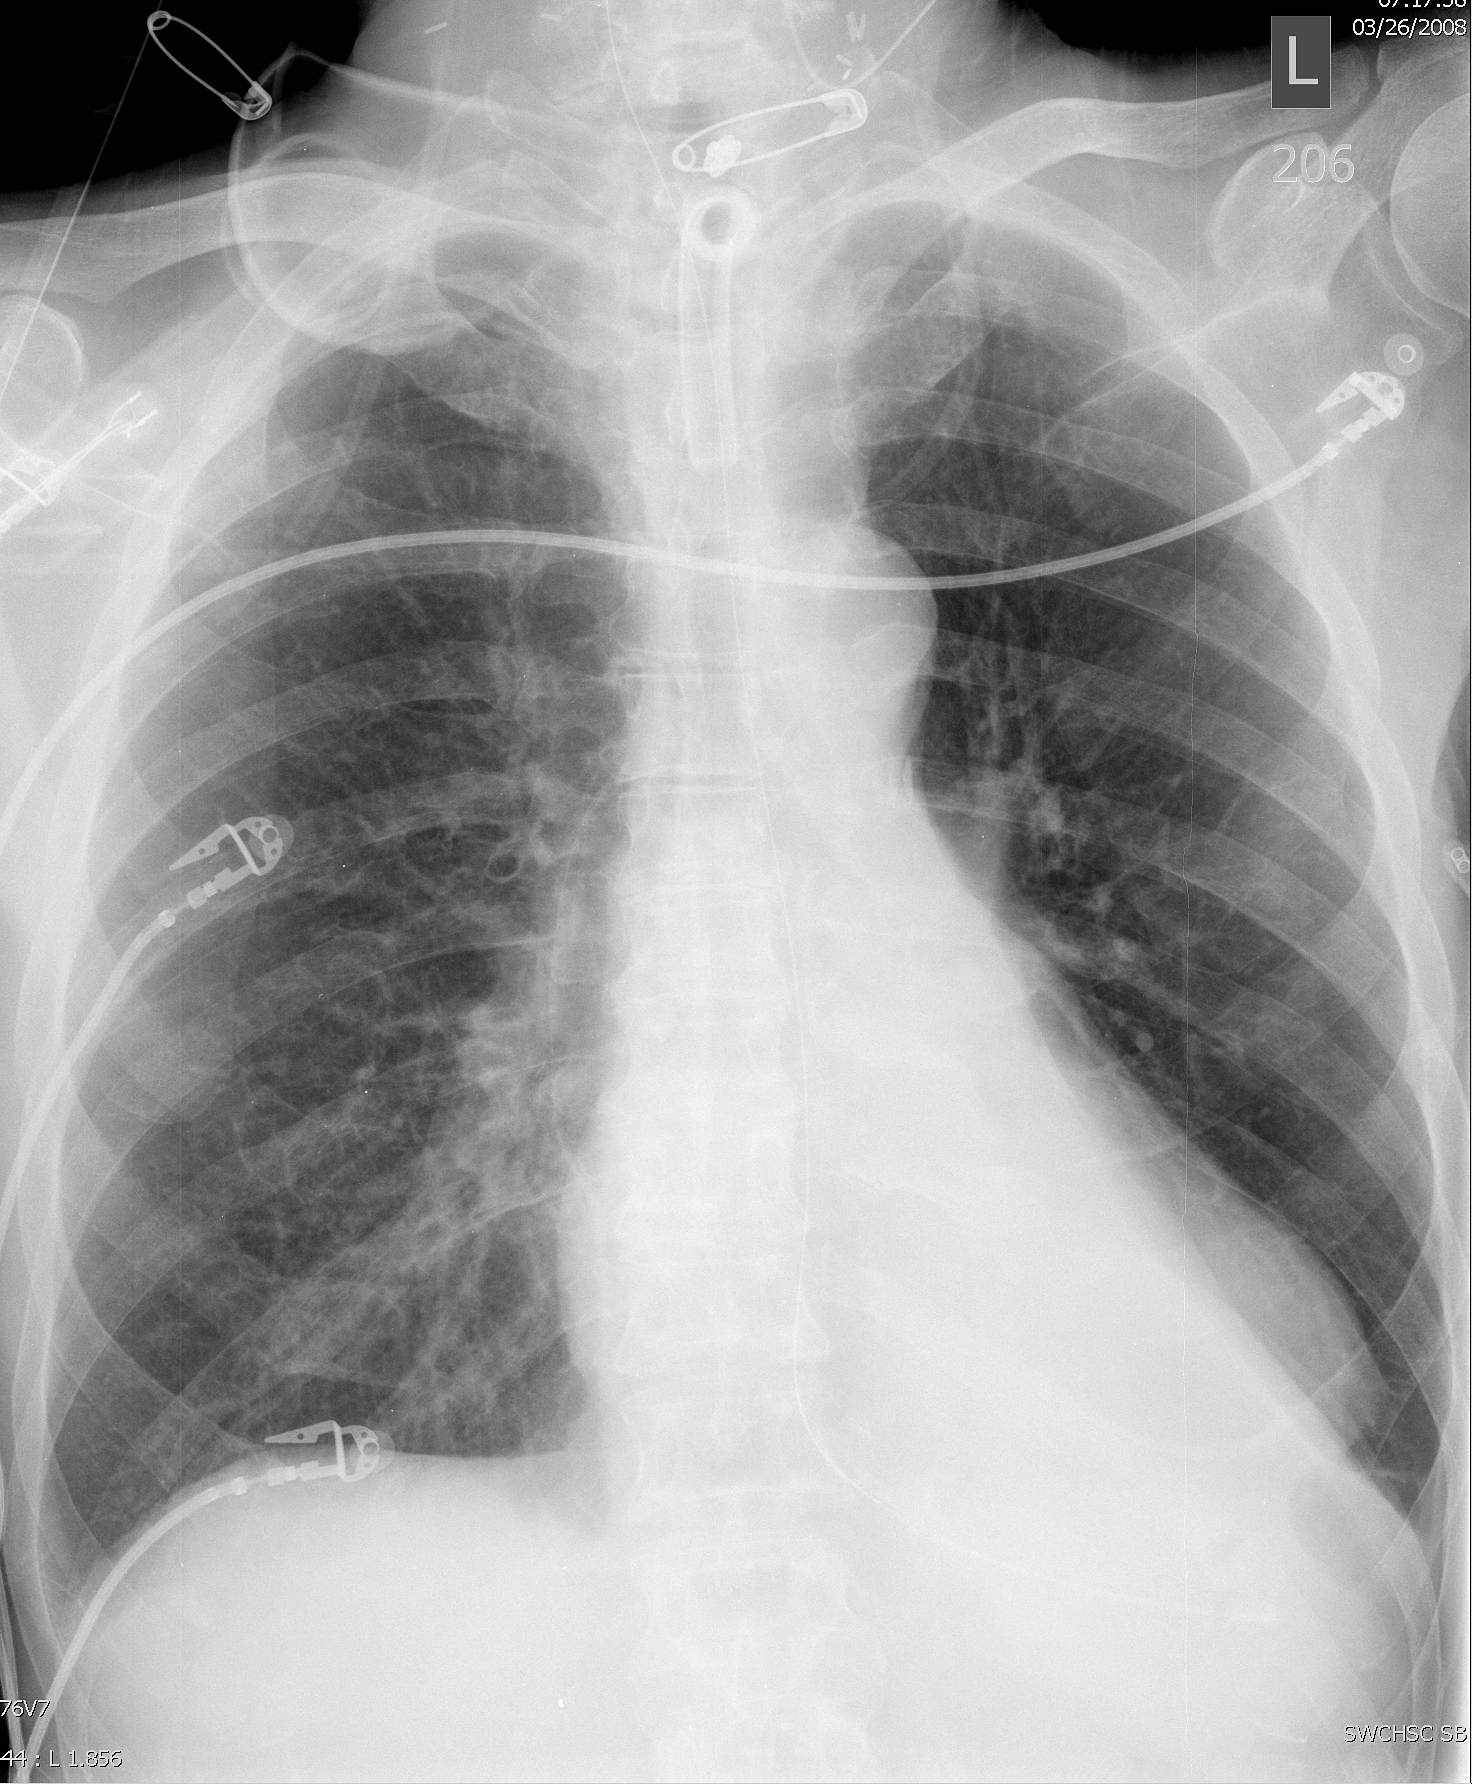

Gallery Lobar Collapse LLL Collapse LLL collapse

LLL collapse